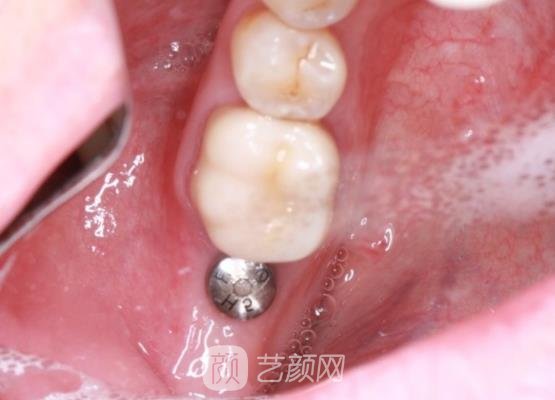

种植牙手术案例:

因为前不久出了一次意外,所以导致我的牙齿出现了缺失的现象,这种情况不但对我的外在形象造成了影响,而且在吃东西的时候真的是特别不方便,感觉嚼什么东西都嚼不动。后来一次偶然的机会知道可以通过种植牙的手术方式去进行改良,所以我也到医院去进行了了解。

在进行手术之前,首先需要选择专业的医院,尽管现在种植牙手术已经很普遍,但是如果医院选择不正规的话,就可能会导致一些不良情况的产生。经过仔细的筛选,我选择在宁波市第二医院来进行调节,因为这家医院的种植牙技术做得很不错,而且医生也有着很不错的口碑。

在手术开始的时候医生为我进行了详细的面诊,并且在面诊环节充分的了解了我的需求,然后为我打造了很适合的种植牙手术方案。手术的整个操作过程很轻松,没有出现什么意外的情况,医生也在手术之后告诉了我一些相关的注意事项,所以我觉得这里的医生真的很负责任。

手术做完之后有一些肿胀的情况,而且在手术之后的短时间之内根本就不敢吃什么东西。医生告诉我这种情况在手术之后是比较正常的一种现象,一般在3~5天左右会得到更好的恢复,说实话这一段时间还是比较难熬的,但是为了让自己的手术变得更加理想一些,我也只能去坚持了。

手术的恢复还算是比较快速的,差不多用了一个月左右的时间,肿胀的情况就得到了很好的消退。虽然现在的手术还没有得到更好的恢复,但是我感觉自己的牙齿也在一天一天的变牢固,现在可以吃一些日常的食物了,再也不需要吃流食来生活,希望手术的恢复能够更快些。

通过自己的亲身经历,真的是对种植牙手术有了很大的改观。之前的时候我觉得种植牙手术肯定不会像自己的真牙一样牢固,而且在吃东西的时候可能也会出现一些不良的情况。但是经过自己的体验感觉种植牙手术之后的改变很大,和真牙一样可以随意的使用,真的是很不错。